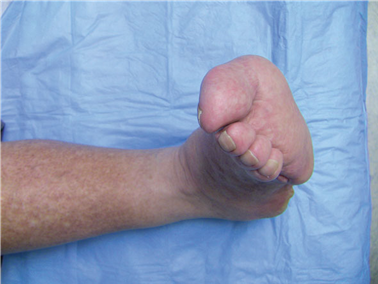

Clinical & Radiographic Imaging Archive

Clinical Image